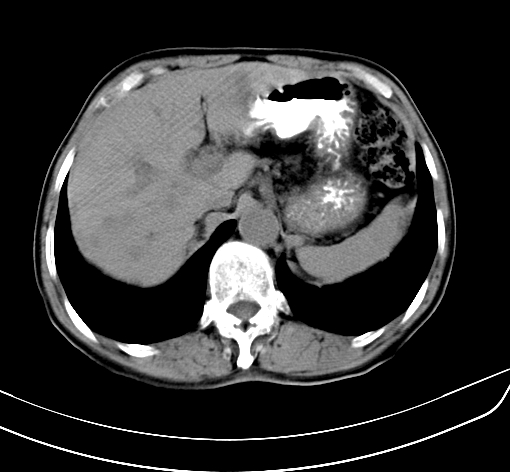

病人 男 70 咳嗽 胃部不适 2月余

胆囊壁增厚,与临近肝实质边界不清,临近肝实质内可见大片边界不清之低密度区,肝门区密度亦有减低,部分结构不清,尾叶前方可见块状影,肝右叶可见多枚边界不清之圆形低密度区,肝内胆管扩张征象,结合病史考虑1胆囊癌肝内转移,肝门区淋巴结转移,门脉癌栓待排2肝内胆管扩张3建议增强扫描

肝脏多发大小不等低密度灶,边界不清,肝门区结构不清,肝内胆管轻度扩张,胆囊密度不均匀,内见软组织样密度影,与相临肝脏边界不清.考虑:1、胆囊ca侵犯肝脏并肝内多发转移,肺上也有结节影,转移?建议强化扫描.2、胃充盈不好,如怀疑有病变最好建议做相关检查.

胆囊壁增厚,周围模糊不清,肝内多发低密度影,胃充盈欠佳,胃壁增厚,外形尚规整,考虑胆囊炎、胆囊癌肝内转移?建议胃肠道进一步检查或增强扫描。